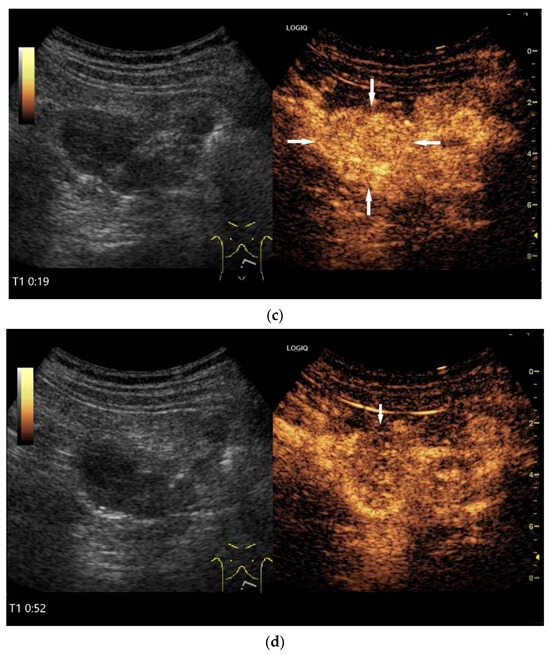

On CEUS all small intestine lymphomas showed arterial enhancement (hyperenhancement in 17 of 18 cases) followed by venous washout. Tumor necrosis was observed in 61% of cases, which occurred more frequently in aggressive subtypes than in indolent subtypes. There was no correlation between tumor size and necrosis [116].

Figure 10.

Diffuse large B-cell lymphoma (DLBCL). In the right mid-lower abdomen, a large, smoothly circumscribed mass is present around the ileum (“pseudo kidney sign” (a)). Using a high-resolution linear transducer, the mass appears smoothly circumscribed and almost anechoic (b). The ileum runs centrally, and the echogenic wall is clearly defined (c). This wall does not merge into the mass. Since the mass is almost anechoic, it is also difficult in different transducer positions to distinguish whether it is a liquid lesion or a solid mass (b,c). CEUS with 2.4 mL SonoVue (9 MHz linear transducer) shows homogeneous arterial enhancement (d), but the intensity decreases with time in the venous phase (e). The ileal wall enhancement centrally within the mass is more intense than that of the tumor (d,e).